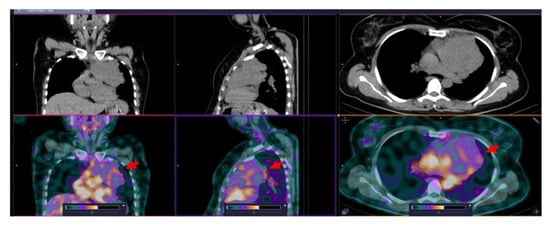

3.3. [99mTc]Tc-TG SPECT/CT Imaging of Nodal and Extranodal Lesions